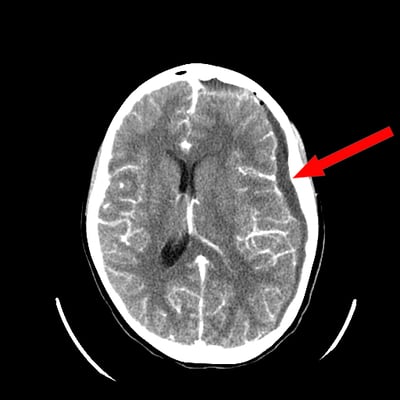

The emergency doctor alerted the Children’s Wisconsin Transport Team to get an ambulance ready. While they waited, they performed a CT scan. The image revealed a collection of fluid on Raynah’s brain. This sac of fluid was so large and creating so much pressure against the left side of her brain that it was pushing it more than a quarter inch out of alignment.

At first they thought it was build-up of blood, possibly caused by a fall or some sort of trauma. Reannyn and Ethan frantically thought back to the preceding days and weeks, but couldn’t think of any such incident. Then the emergency doctor came back into the room and revealed the answer — it wasn’t blood, it was pus.

Raynah had a large collection of infected fluid on her brain, known as a subdural empyema. The CT scan showed that her sinuses, too, were completely packed with infection. A brain infection of that nature on an otherwise healthy kid is extremely rare. In fact, fewer than 20,000 cases occur annually in the United States. Children’s Wisconsin treats less than five cases every year.